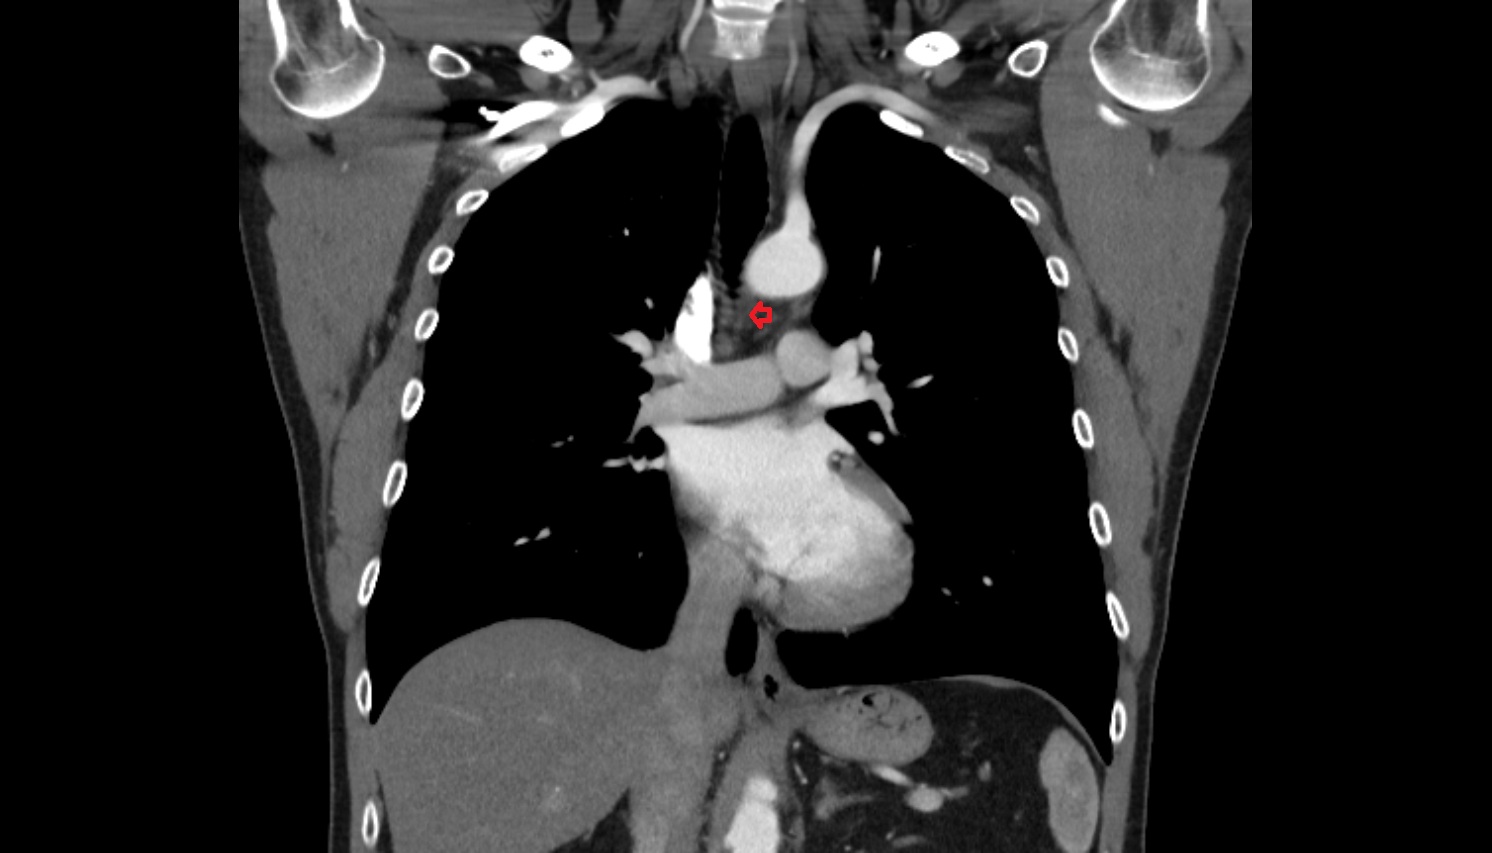

- Ascending aorta

- Arch of aorta

- Descending thoracic aorta